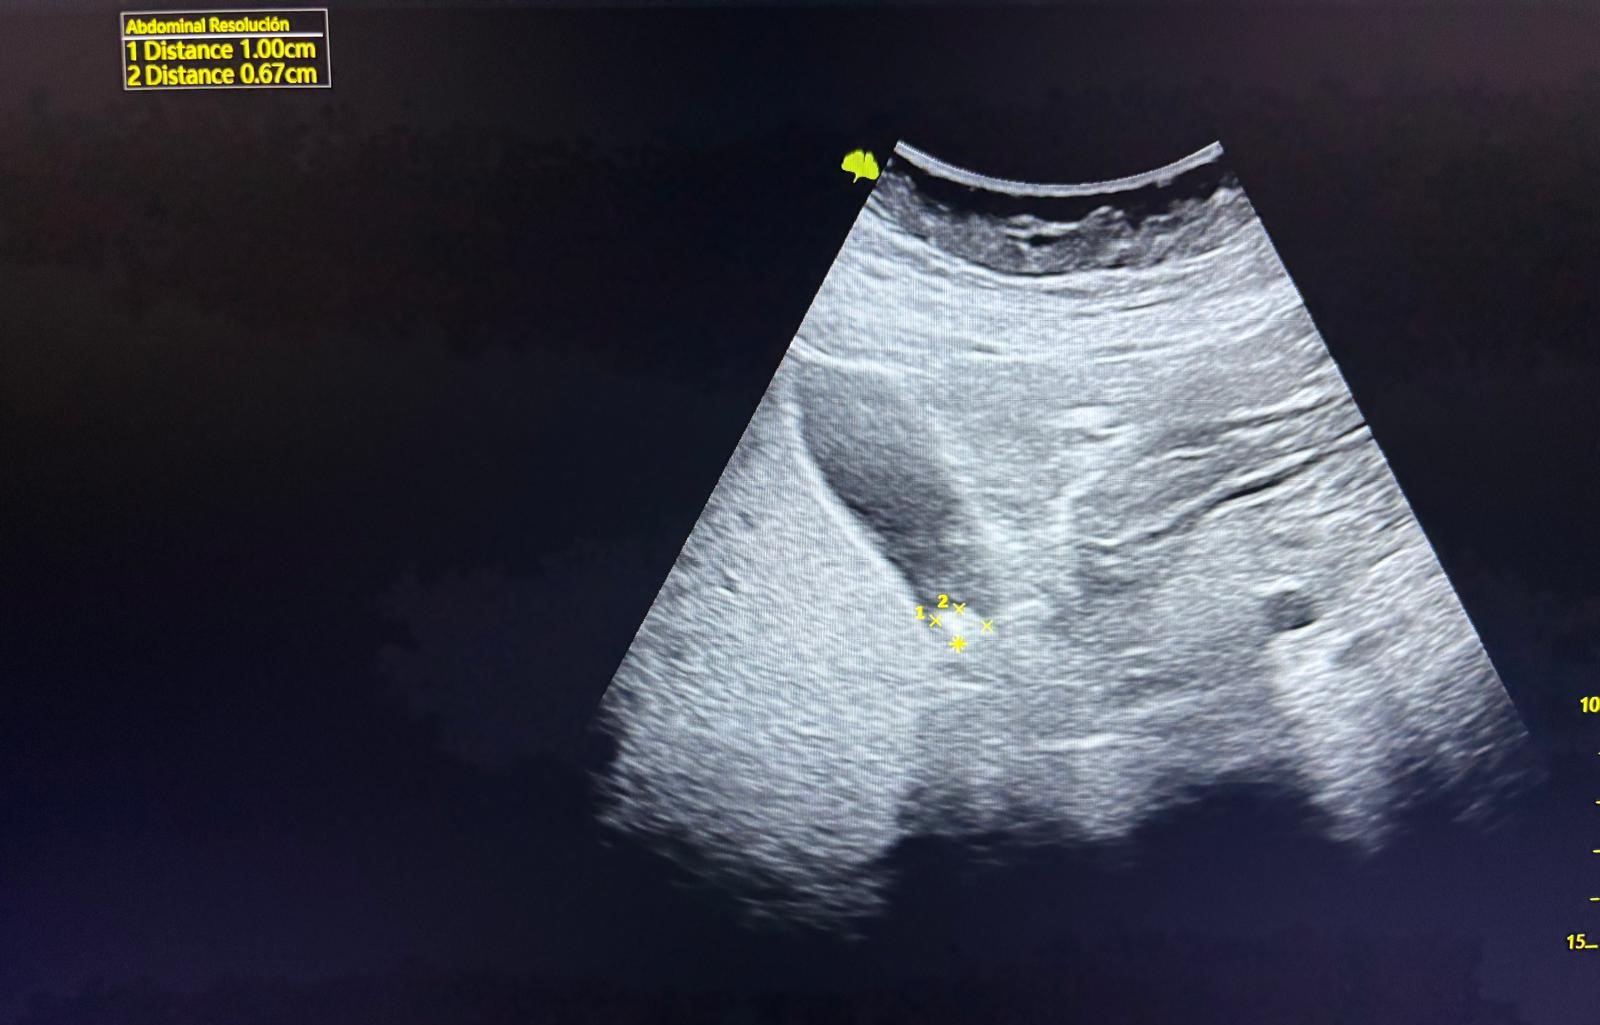

Hallazgos ecográficos

Vesícula biliar de 5,89 x 2,74 cm no distendida, paredes finas de 0,23 cm. Se visualiza imagen hiperecogénica redondeada única de 1 x 0,67 cm en infundíbulo con sombra posterior sugestiva de litiasis.